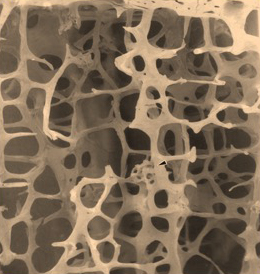

Osteoporose is de medische naam voor poreus bot ofwel zwak bot. Zwak wil zeggen, zwakker dan het gemiddelde. Osteoporose is een aandoening van het skelet, waarbij de botsterkte afneemt. Dit komt door een afname van de botdichtheid en door een verslechtering van de botstructuur. Het bot wordt dus zowel lichter als zwakker. Door de afname van de botsterkte neemt de kans op schade aan de botten toe.

Gezonde botstructuur

Osteoporose